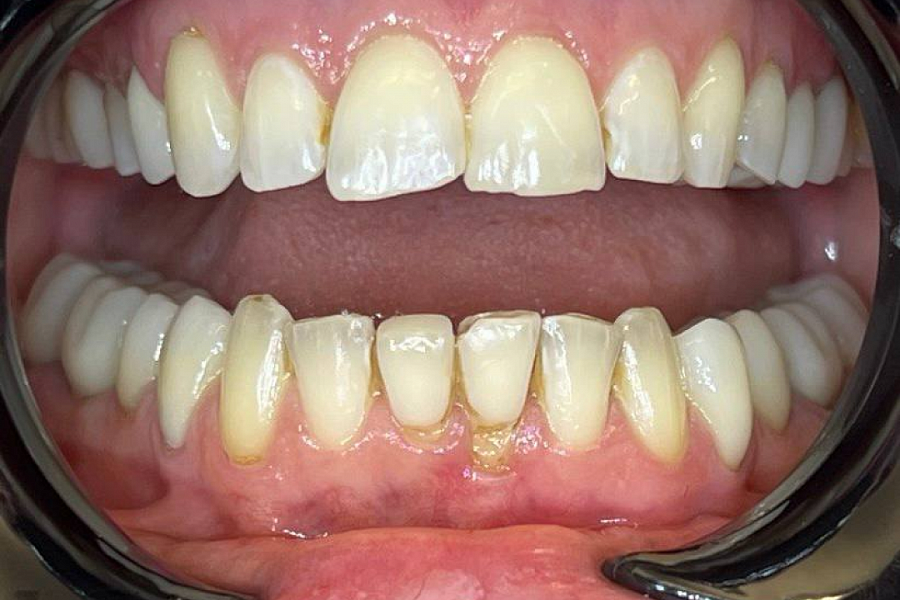

Сначала было проведена санация полости рта. Затем а ортодонтическое лечение для восстановления высоты прикуса.

С эстетической частью справились за счёт протезирования винирами в естественной форме и в естественном цвете.

Результат получился отличный! Пациентка очень довольна!